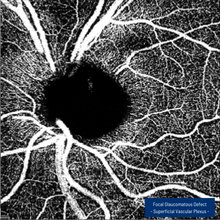

The SPECTRALIS®OCT Angiography Module delivers high-resolution OCTA images with a lateral resolution of 5.7 μm/pix. Combined with the precision of TruTrack Active Eye Tracking, the OCTA Module enables fine capillary networks to be visualized in great detail.

The axial resolution of 3.9 μm/ pixel allows for segmentation of all four histologically-validated retinal vascular plexuses. Custom slabs within the superficial and deep vascular plexuses offer a more comprehensive clinical evaluation.

The projection artifact removal (PAR) tool utilizes information from the superficial vascular plexus to remove artifacts from OCTA images. This enables a more precise visualization of vascular structure and pathology.